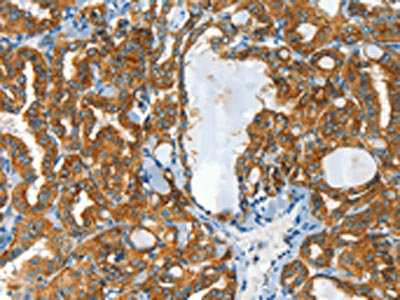

• The image on the left is immunohistochemistry of paraffin-embedded Human thyroid cancer tissue using CSB-PA930031(CLPTM1L Antibody) at dilution 1/60, on the right is treated with synthetic peptide. (Original magnification: ×200)

• The image on the left is immunohistochemistry of paraffin-embedded Human liver cancer tissue using CSB-PA930031(CLPTM1L Antibody) at dilution 1/60, on the right is treated with synthetic peptide. (Original magnification: ×200)